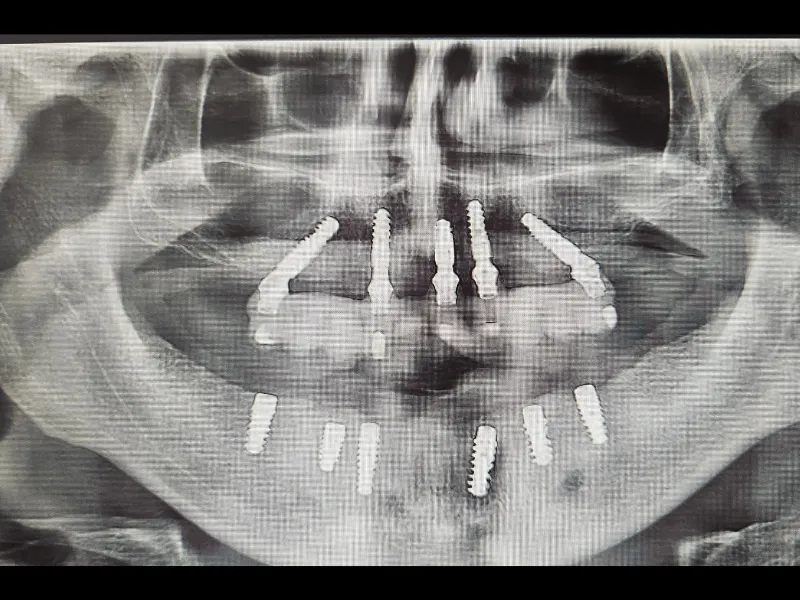

U zavisnosti od individualne anatomije i kliničke situacije, određuje se optimalan broj i raspored implantata (4, 5 ili 6), čime se postiže stabilna osnova za fiksnu protetsku konstrukciju. Ovakav pristup omogućava precizno planiranje i maksimalnu funkcionalnost za svakog pacijenta.

Implantati se postavljaju u vilicu i služe kao stabilna osnova za fiksnu protetsku konstrukciju. Broj implantata (4, 5 ili 6) određuje se individualno, u skladu sa anatomijom, funkcionalnim i estetskim zahtjevima pacijenta.

Zahvaljujući preciznom planiranju i organizaciji terapije, moguće je u kratkom vremenskom periodu realizovati ključne faze ALL-ON-X zahvata. Ova procedura omogućava brzu funkcionalnu i estetsku rehabilitaciju, što je čini pogodnom i za pacijente koji dolaze iz inostranstva.